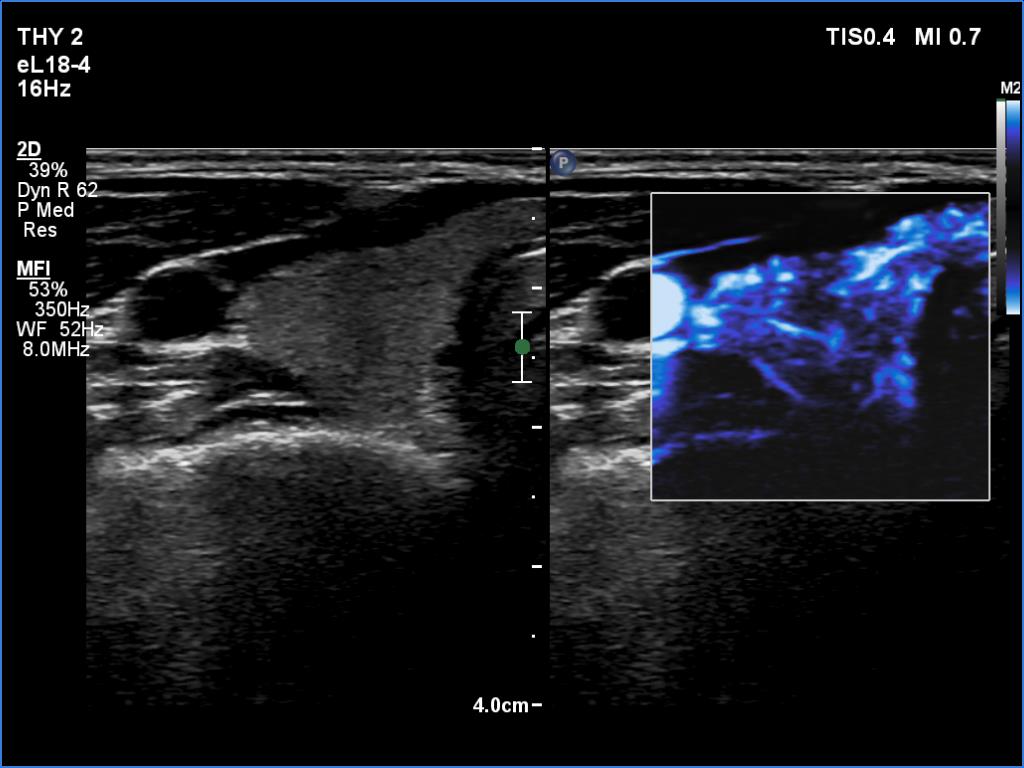

Case 1348 (ultrasonographic picture 4)

Right lobe, trasnverse scan, microflow imaging.